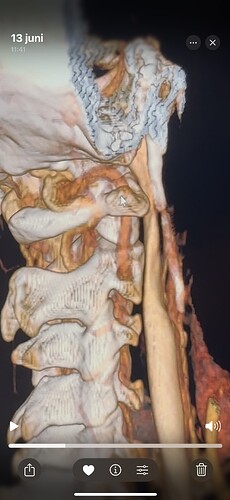

I have a cbct and CVA made wich shows elongated styloids and calcified stylohoids around 5 cm. Space left in neutral position between c1 is 3.5mm. Left IJV compression in laying position but there seems to be mainly some soft tissue compression there. So not due to compression of c1/styloid. The right is my dominant IJV.

Hi Rob & welcome! Looking at your CT, & obviously we’re not experts, I would estimate that your styloid & calcified ligament section is longer than 5 cm; on your left in the middle image it goes way past your C2 vertebra! We have found that the measurements from CTs are often wrong as it can be quite hard to measure accurately due to CT imaging being done in slices…

The IJVs do collapse naturally when flat, so it could be due to that, in your 3rd image it looks like the IJV is flattened higher up, so what would be right by the skull base. It could be like that naturally because of being flat for the CT, or it could be that it is being compressed where it emerges from the skull at the jugular foramen - if styloids are quite thick that is possible, & yours do look a little wide at the top… It looks like there could be something pinching the IJV between it & the styloid where you’ve marked too; we’ve had members who’ve had compression from an enlarged SCM muscle, the digastric muscle, omahyoid muscle, as well as other blood vessels & nerves… I’d guess where the compression is that the digastric muscle would be the most likely if it was a muscle, or maybe the stylohyoid muscle, although we don’t hear much about that one!

@Rob12345 - Welcome to our forum! I have nothing to add to what @Jules said, but did want to say WOW! You do have very long styloids. The “kink” in your ICA (internal carotid) isn’t really a kink more of a curve, but I can see based on the image, that it could be causing some slowed or backed up blood flow going into your brain. The IJV compression is curious as it appears to be more than the styloid causing the problem but clearly C1 seems not to be involved. I think Jules has made some logical assumptions regarding other possible compression culprits.

@Rob12345 - I can see you have bilateral IJV compression in the images you’ve posted & it’s possible the middle image in your first set of pictures is pointing to collateral veins. I’m not great at identifying collaterals, but I can say for sure your IJVs are being squashed between your styloids & C1.